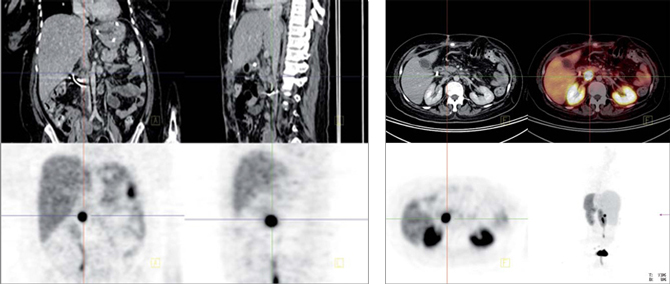

Tumores gastroenteropancreáticos

Este grupo (GEP) constituyen un grupo heterogéneo de tumores neuroendocrinos del estómago, páncreas e intestino. El más frecuente es el tumor carcinoide. El tratamiento primario es la cirugía aún en los pacientes con enfermedad metastásica, debido a que la resección parcial puede mejorar la calidad de vida, sobrevida y estado funcional. Las imágenes cumplen un papel importante para determinar la extensión de la enfermedad al inicio y en el seguimiento. Los estudios realizados con 111In pentatreotide muestran elevada sensibilidad para la detección de GEP a excepción del insulinoma. La sensibilidad para el gastrinoma metastásico, carcinoide y otros GEP son generalmente sobre 80% hasta 94%. La sensibilidad para la enfermedad metastásica tiende a ser superior a la de los tumores primarios (Figura 1) y en muchas ocasiones se encuentran lesiones no detectables por imágenes anatómicas. Utilizando Ga68 análogos de somatostatina se han obtenido excelentes resultados, con sensibilidades entre 82-100% (Figuras 2 y 3). El FDG tiene baja sensibilidad para la detección de estos tumores de lento crecimiento, bien diferenciados y bajo Ki-67, en cambio las imágenes con análogos de somatostatina presentan un patrón opuesto (Figura 4 y 5). Los tumores neuroendocrinos indiferenciados y agresivos presentan marcada avidez por la glucosa y pobre expresión de receptores de somatostatina y viceversa. Se ha visto que los pacientes con tumores con mayor expresión de Ki-67 evolucionan peor que aquellos con bajo Ki-6715. Los tumores neuroendocrinos que captan FDG tienen por lo tanto peor pronóstico16. En un estudio que comparó el rendimiento de cintigrafía con Octreoscan y FDG en pacientes con tumor carcinoide encontró que el 86% de los tumores primarios se localizaban con pentatreotide mientras que sólo el 57% con FDG. Pacientes con metástasis, el 69% fue positivo con el análogo de somatostatina, 47% con FDG y 56% con imágenes anatómicas17. Figuras similares se han obtenido con el uso de PET y Ga68análogos de somatostatina18,19.